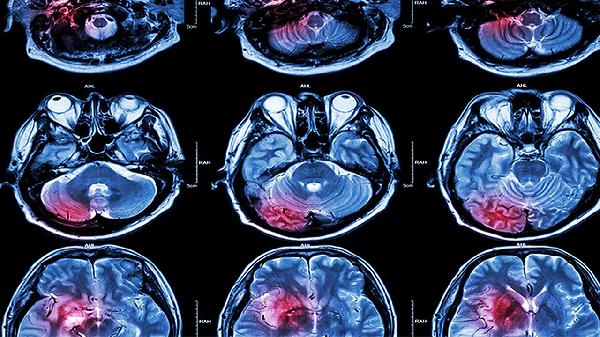

脑溢血可能由高血压、脑血管畸形、动脉瘤、血液病、外伤等因素引起。脑溢血通常表现为头痛、呕吐、意识障碍、肢体无力等症状,严重时可危及生命。建议及时就医,积极配合医生治疗,在医生的指导下服用合适的药物,并做好饮食调理。

脑血管畸形是指脑血管发育异常,包括动静脉畸形、海绵状血管瘤等。这些异常的血管结构脆弱,容易破裂出血。脑血管畸形引起的脑溢血可能没有明显诱因,患者可能出现癫痫发作、局灶性神经功能缺损等症状。治疗脑血管畸形可采用手术切除、血管内介入栓塞等方法,常用药物有甘露醇注射液、呋塞米注射液等降低颅内压。

脑动脉瘤是脑血管壁的局部膨出,随着血压波动可能突然破裂导致脑溢血。动脉瘤破裂引起的脑溢血常表现为突发剧烈头痛、颈项强直、意识障碍等症状。治疗脑动脉瘤可采用开颅夹闭术或血管内介入栓塞术,术后可能需要使用尼莫地平片预防脑血管痉挛。